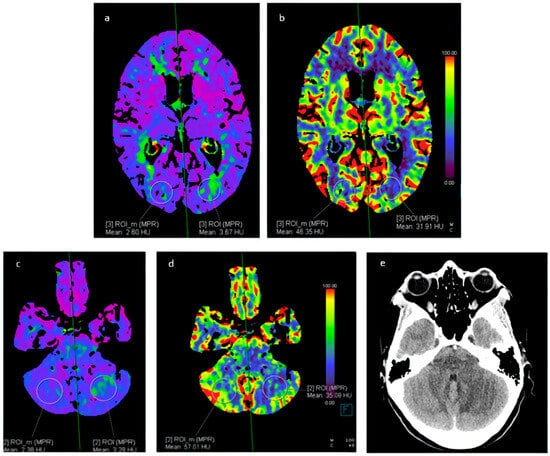

Alternatively, arterial spin-labeling perfusion is a completely non-invasive MRI technique that does not require the administration of gadolinium contrast. Instead, it utilizes electromagnetic spin inversion to label water molecules, which then act as freely diffusible flow tracers [10] (Figure 4).

Figure 4. A 37-year-old female with cocaine-induced RCVS, admitted to the Emergency Department due to headache and bilateral hypovision. Perfusion CT showed (a,b) an increased TMAX and reduced CBF in the left occipital lobe; (c,d) an increased TMAX and a reduced CBF in the left cerebellar hemisphere. (e) CT showed a cerebral infarct on the left cerebellar hemisphere corresponding to the area indicated on perfusion CT. RCVS: reversible cerebral vasoconstriction syndrome. TMAX: time-to-maximum. CBF: cerebral blood flow.